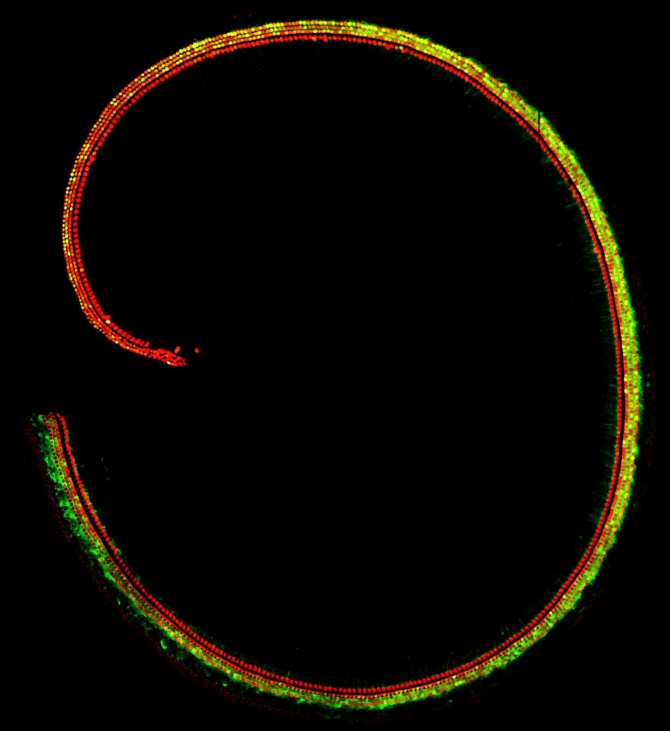

Imagen microscópica de la cóclea de un ratón. Las células ciliadas están teñidas de rojo y las células en las que ha actuado el virus reparador están teñidas de verde. (Foto: Shahar Taiber, Tel Aviv University)

Un equipo que incluye a Karen Avraham y Shahar Taiber, ambos de la Universidad de Tel Aviv en Israel, se concentró en la sordera causada por una mutación en el gen SYNE4, una sordera poco común descubierta por el laboratorio de Avraham hace varios años en dos familias israelíes, y desde entonces identificada también en personas de Turquía y del Reino Unido. Los niños que heredan el gen defectuoso de ambos progenitores nacen con una capacidad auditiva normal, pero la pierden gradualmente durante la infancia. La mutación causa una mala ubicación de los núcleos celulares en las células ciliadas dentro de la cóclea del oído interno, que sirven como receptores de las ondas sonoras y resultan esenciales para la audición. Este defecto conduce al deterioro de las células ciliadas y finalmente a su muerte.

Avraham y sus colegas idearon una terapia genética para tratar esa sordera y la probaron en ratones. Prepararon un virus sintético inofensivo y lo usaron para suministrar material genético (una versión normal del gen que es defectuoso tanto en el modelo de ratón como en las familias humanas afectadas). Inyectaron el virus en el oído interno de los ratones, de modo que entró en las células ciliadas del oído interno y liberó en ellas su carga genética. Gracias a ello, se reparó el defecto en las células ciliadas y estas pudieron madurar debidamente y funcionar con normalidad.